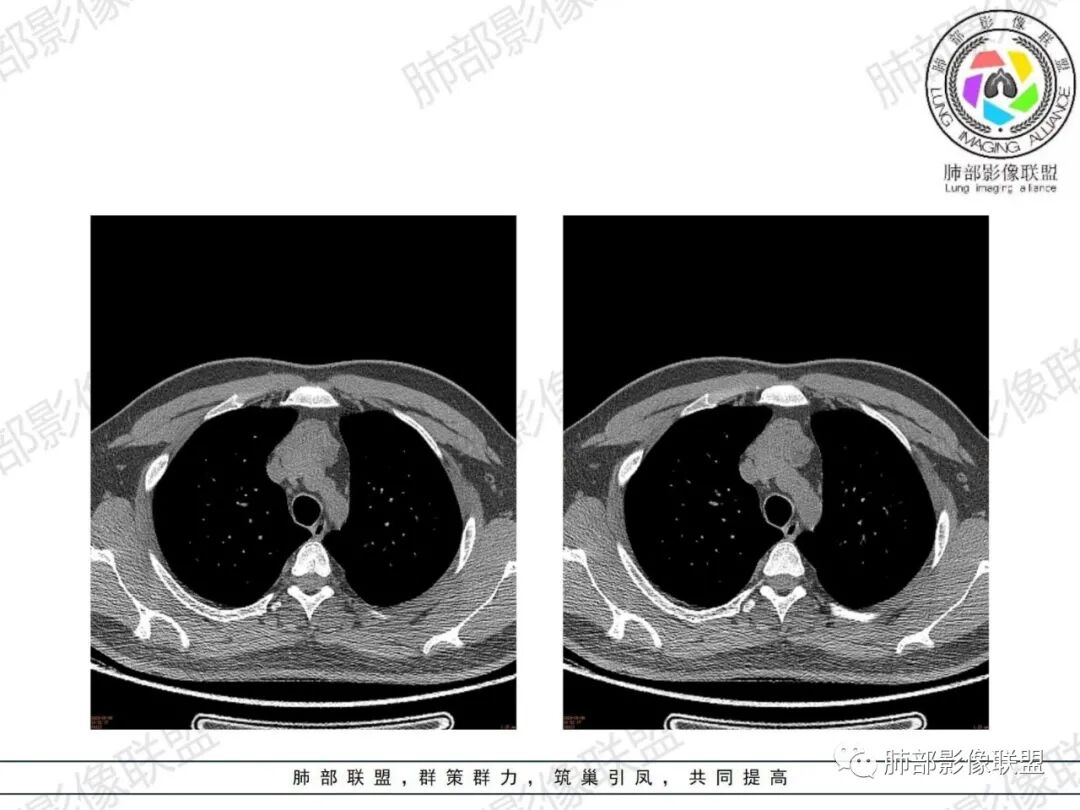

胸腺增生CT表现

体积、形态:

弥漫性增大,两缘对称,质地柔软,部分淋巴性胸腺增生的大小正常;形态保持其正常形态,呈类圆形、梨形,边缘光滑,可呈浅分叶

密度:

密度均匀,呈肌性密度,偶见细小钙化,其内有脂肪浸润样密度影

强化:

轻度或无强化

与周围结构关系:

与周围大血管、胸骨等周围组织结构分界清楚,无淋巴结肿大、胸膜及心包受累。

1、年轻男性,双下肌乏力,胸部CT提示前纵隔胸腺区病变,应当怀疑胸腺增生或胸腺瘤导致的重症肌无力。

2、前纵隔梨形软组织密度影,与正常胸腺形态一致,为胸腺弥漫性增大,两缘匀称,质地柔软,未见明显膨隆,其内可见脂肪浸润影,与周围结构分界清楚,再加上病人年龄,需要高度提示胸腺增生(淋巴滤泡样增生型)。胸腺瘤一般无脂肪浸润,质地较硬,呈结节或肿块状,且发病年龄较大。B2B3型肿块边界不清,可侵犯临近组织脏器,B3可胸膜转移,胸腺癌可引起纵隔淋巴结及远处转移。